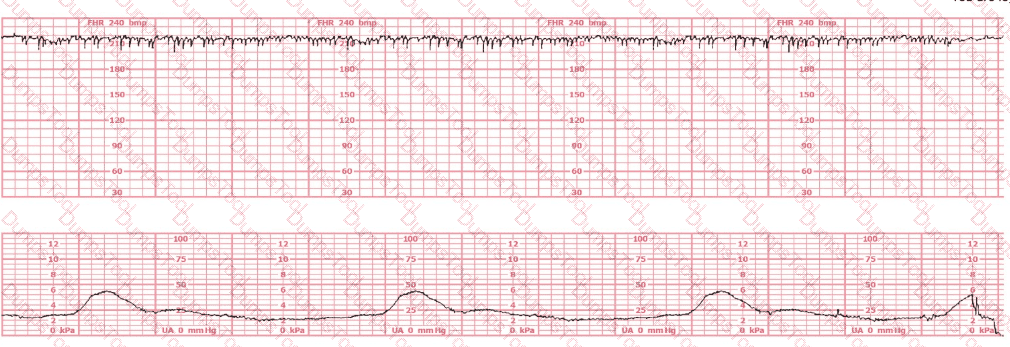

A woman at 39-weeks gestation is being induced. She has chronic hypertension controlled by methyldopa (Aldomet). Spontaneous rupture of membranes has occurred; she is 10 cm dilated and at +1 station. The fetal monitor tracing shown is obtained by spiral electrode and tocodynamometer. The next best appropriate action is to:

A nulliparous woman at term presents with leaking fluid. Rupture of membranes confirmed. After 6 hours she is completely dilated, +2 station, has been pushing 2 hours with oxytocin at 10 mU/min. The fetal tracing is shown. What is the next step in management?

This fetal heart rate tracing is from a woman in the second stage of labor. This tracing is best interpreted as: